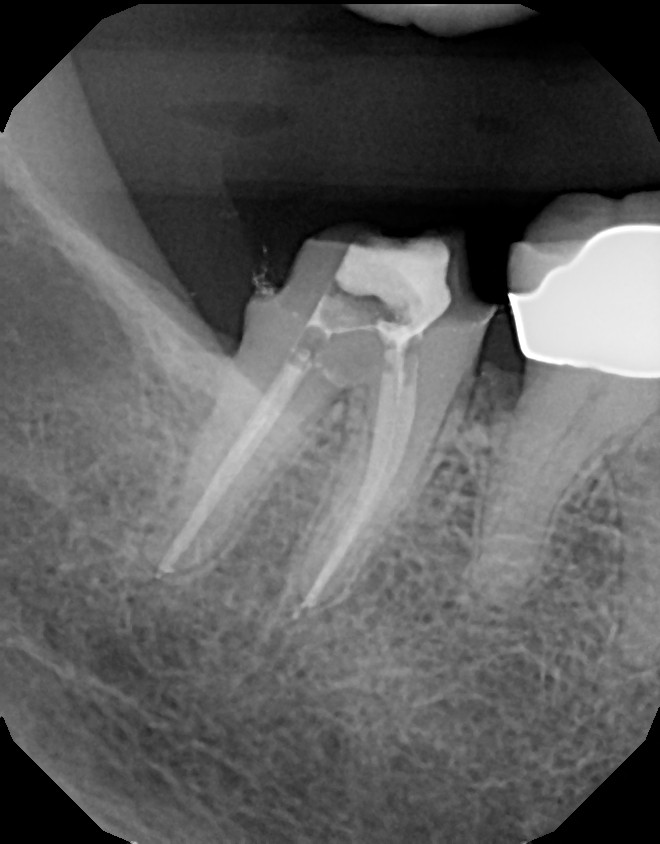

Below are pictures of a recent case of mine. This 10+ year old crown that developed decay (cavity) around the margin where tooth meets crown. Always pay attention to sensitivity around fillings and crowns and advise your dentist when symptoms develop, so you can stay away from roots canals. In this particular case, root canal was required because the decay reached too close to the nerve.